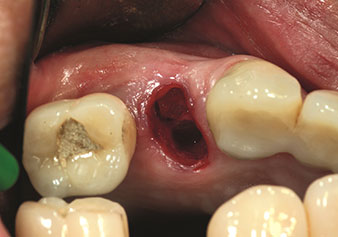

Situation following piezosurgical extraction

Fig. 2: Situation following piezosurgical extraction. Photo: © Dr Torsten Conrad (Bingen am Rhein)

One application, which is often underestimated is the atraumatic extraction of tooth roots or root fragments in the scope of alveolar management. The fine periotomes, which are currently available in two versions (EX1 and EX2 from W&H), can also be used to remove teeth which have previously undergone special endodontic treatment or ankylosed roots with ease. This results in extraction alveoli where both the hard and soft tissue are fully intact as it is generally possible to avoid reflection.

This establishes the optimal basis for subsequent or immediate implant treatment (Figures 1 and 2 included with the kind permission of Dr Torsten Conrad, Bingen a. Rhein).